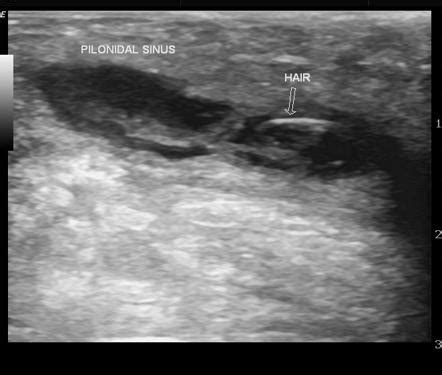

Ultrasound: The Go-To Imaging Modality

When it comes to imaging a pilonidal abscess , ultrasound is often the first tool in the radiologist’s toolkit, and for good reason, guys. It’s readily available, relatively inexpensive, and provides excellent real-time visualization of soft tissues, making it fantastic for detecting fluid collections like those pesky abscesses. The way ultrasound works is by bouncing sound waves off your body’s tissues and then interpreting the echoes to create an image. For a pilonidal abscess, the sonographer will use a transducer, which is like a wand, and apply a gel to the skin over the affected area. This gel helps to get good contact and transmit the sound waves effectively. As they move the transducer around, they’ll be looking for specific signs. The abscess itself typically appears as a well-defined, anechoic or hypoechoic area – basically, a dark or grayish area on the ultrasound screen, indicating a fluid-filled space. You might also see thickened walls around this collection, which signifies the body’s inflammatory response. The beauty of ultrasound is its ability to differentiate between solid and cystic structures. So, it can confirm that what they’re seeing is indeed an abscess filled with pus, rather than a solid tumor or other mass. Furthermore, ultrasound can help assess the size of the abscess, its depth, and its relationship to nearby structures, like muscles or blood vessels. This information is crucial for surgical planning, helping the surgeon decide on the best approach for drainage or excision. In some cases, ultrasound can even be used during the drainage procedure, guiding the needle precisely into the abscess cavity to ensure complete evacuation of the pus. This real-time guidance is a huge advantage. While ultrasound is great, it’s important to remember that it’s highly dependent on the skill of the sonographer and can sometimes be limited in obese patients or if there’s a lot of gas in the bowel overlying the area. But generally speaking, for initial evaluation and confirmation of a pilonidal abscess, ultrasound is a true workhorse in the radiology department.

Interpreting the Findings: What Radiologists Look For

So, when a radiologist looks at the images – be it an ultrasound, CT, or MRI – of a suspected pilonidal abscess , what are they specifically searching for? Guys, it’s like a detective hunt for clues! The primary goal is to confirm the presence of an abscess, which is essentially a collection of pus. On imaging, this typically appears as a well-defined area of fluid. In ultrasound , it’s often seen as a dark (anechoic) or mixed-echogenicity area with potentially thickened walls. On CT and MRI , these collections usually show up as areas of low signal intensity on certain sequences, often with a rim that enhances brightly after contrast administration, indicating inflammation. Another key thing radiologists look for is the size and extent of the abscess. Is it a small, localized collection, or is it a large, sprawling one? This information directly influences how it will be managed. They also assess its location relative to important anatomical structures. Is it superficial, or is it deep? Is it near the midline, or off to one side? This helps surgeons plan their approach. A critical finding, especially in recurrent cases, is the presence of sinus tracts . These are abnormal tunnels that can extend from the abscess or the original pit in the skin. Radiologists meticulously look for these tracts, as their identification is crucial for successful surgical treatment. They might appear as thin, linear areas of abnormal enhancement after contrast. The radiologist will describe the course, length, and any branching of these tracts. Finally, they are on the lookout for associated findings that might indicate a more complex situation. This could include surrounding inflammation of the skin and subcutaneous tissues (cellulitis), evidence of bone infection (osteomyelitis, though rare), or other rare complications. Interpreting these findings requires a deep understanding of both anatomy and pathology, making the radiology report a vital piece of the puzzle for the treating physician managing the pilonidal abscess . The radiologist’s detailed description helps paint a clear picture, guiding the clinician towards the most appropriate and effective treatment strategy for the patient.